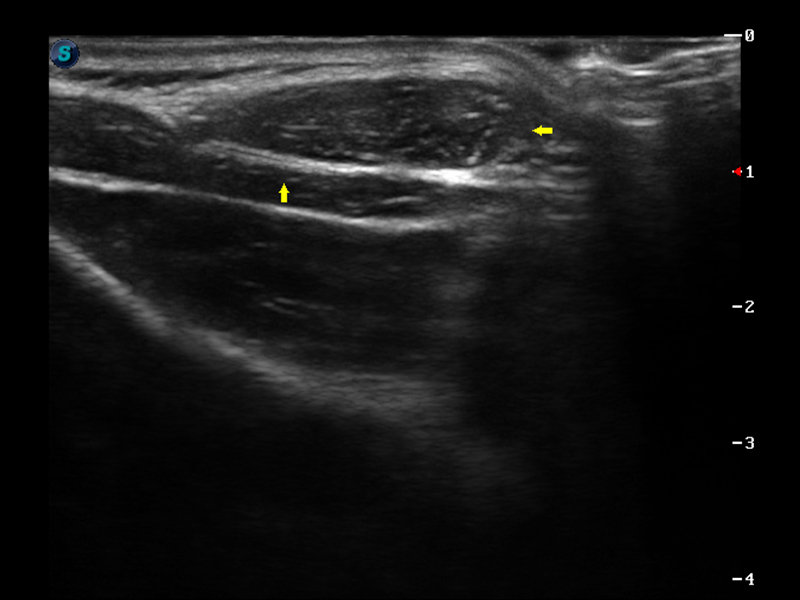

S9便携式彩色多普勒超声诊断仪是1xBET研发的高端便携彩超设备,外观设计新颖、产品性能卓越。S9在便携超声领域采用了突破传统的触摸屏交互设计,并以先进的软件硬件技术和设计理念,为您带来清晰的图像质量、稳定的工作性能和便捷的操作体验。

μ-Scan微米成像